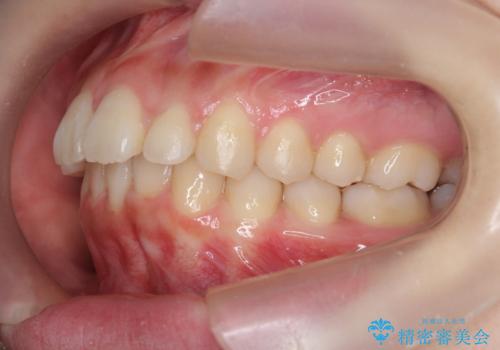

マウスピースで出っ歯感の改善

- 上の前歯が出ている感じを治したい、と矯正治療を希望され来院されました。

上顎歯列の突出感を改善すべくIPRを行い、下顎歯列を小さくすることで前歯の角度を大きく是正します、。

下顎歯列は元々前歯が1本少なく小さなアーチでしたが、下顎に合わせ上顎歯列もIPRを行い小さくすることで出っ歯感を大きく改善することが出来ました。